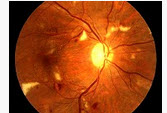

原发性高血压(如图)患者约有多少可以引起眼底改变()

A:40%

B:50%

C:60%

D:70%

E:80%